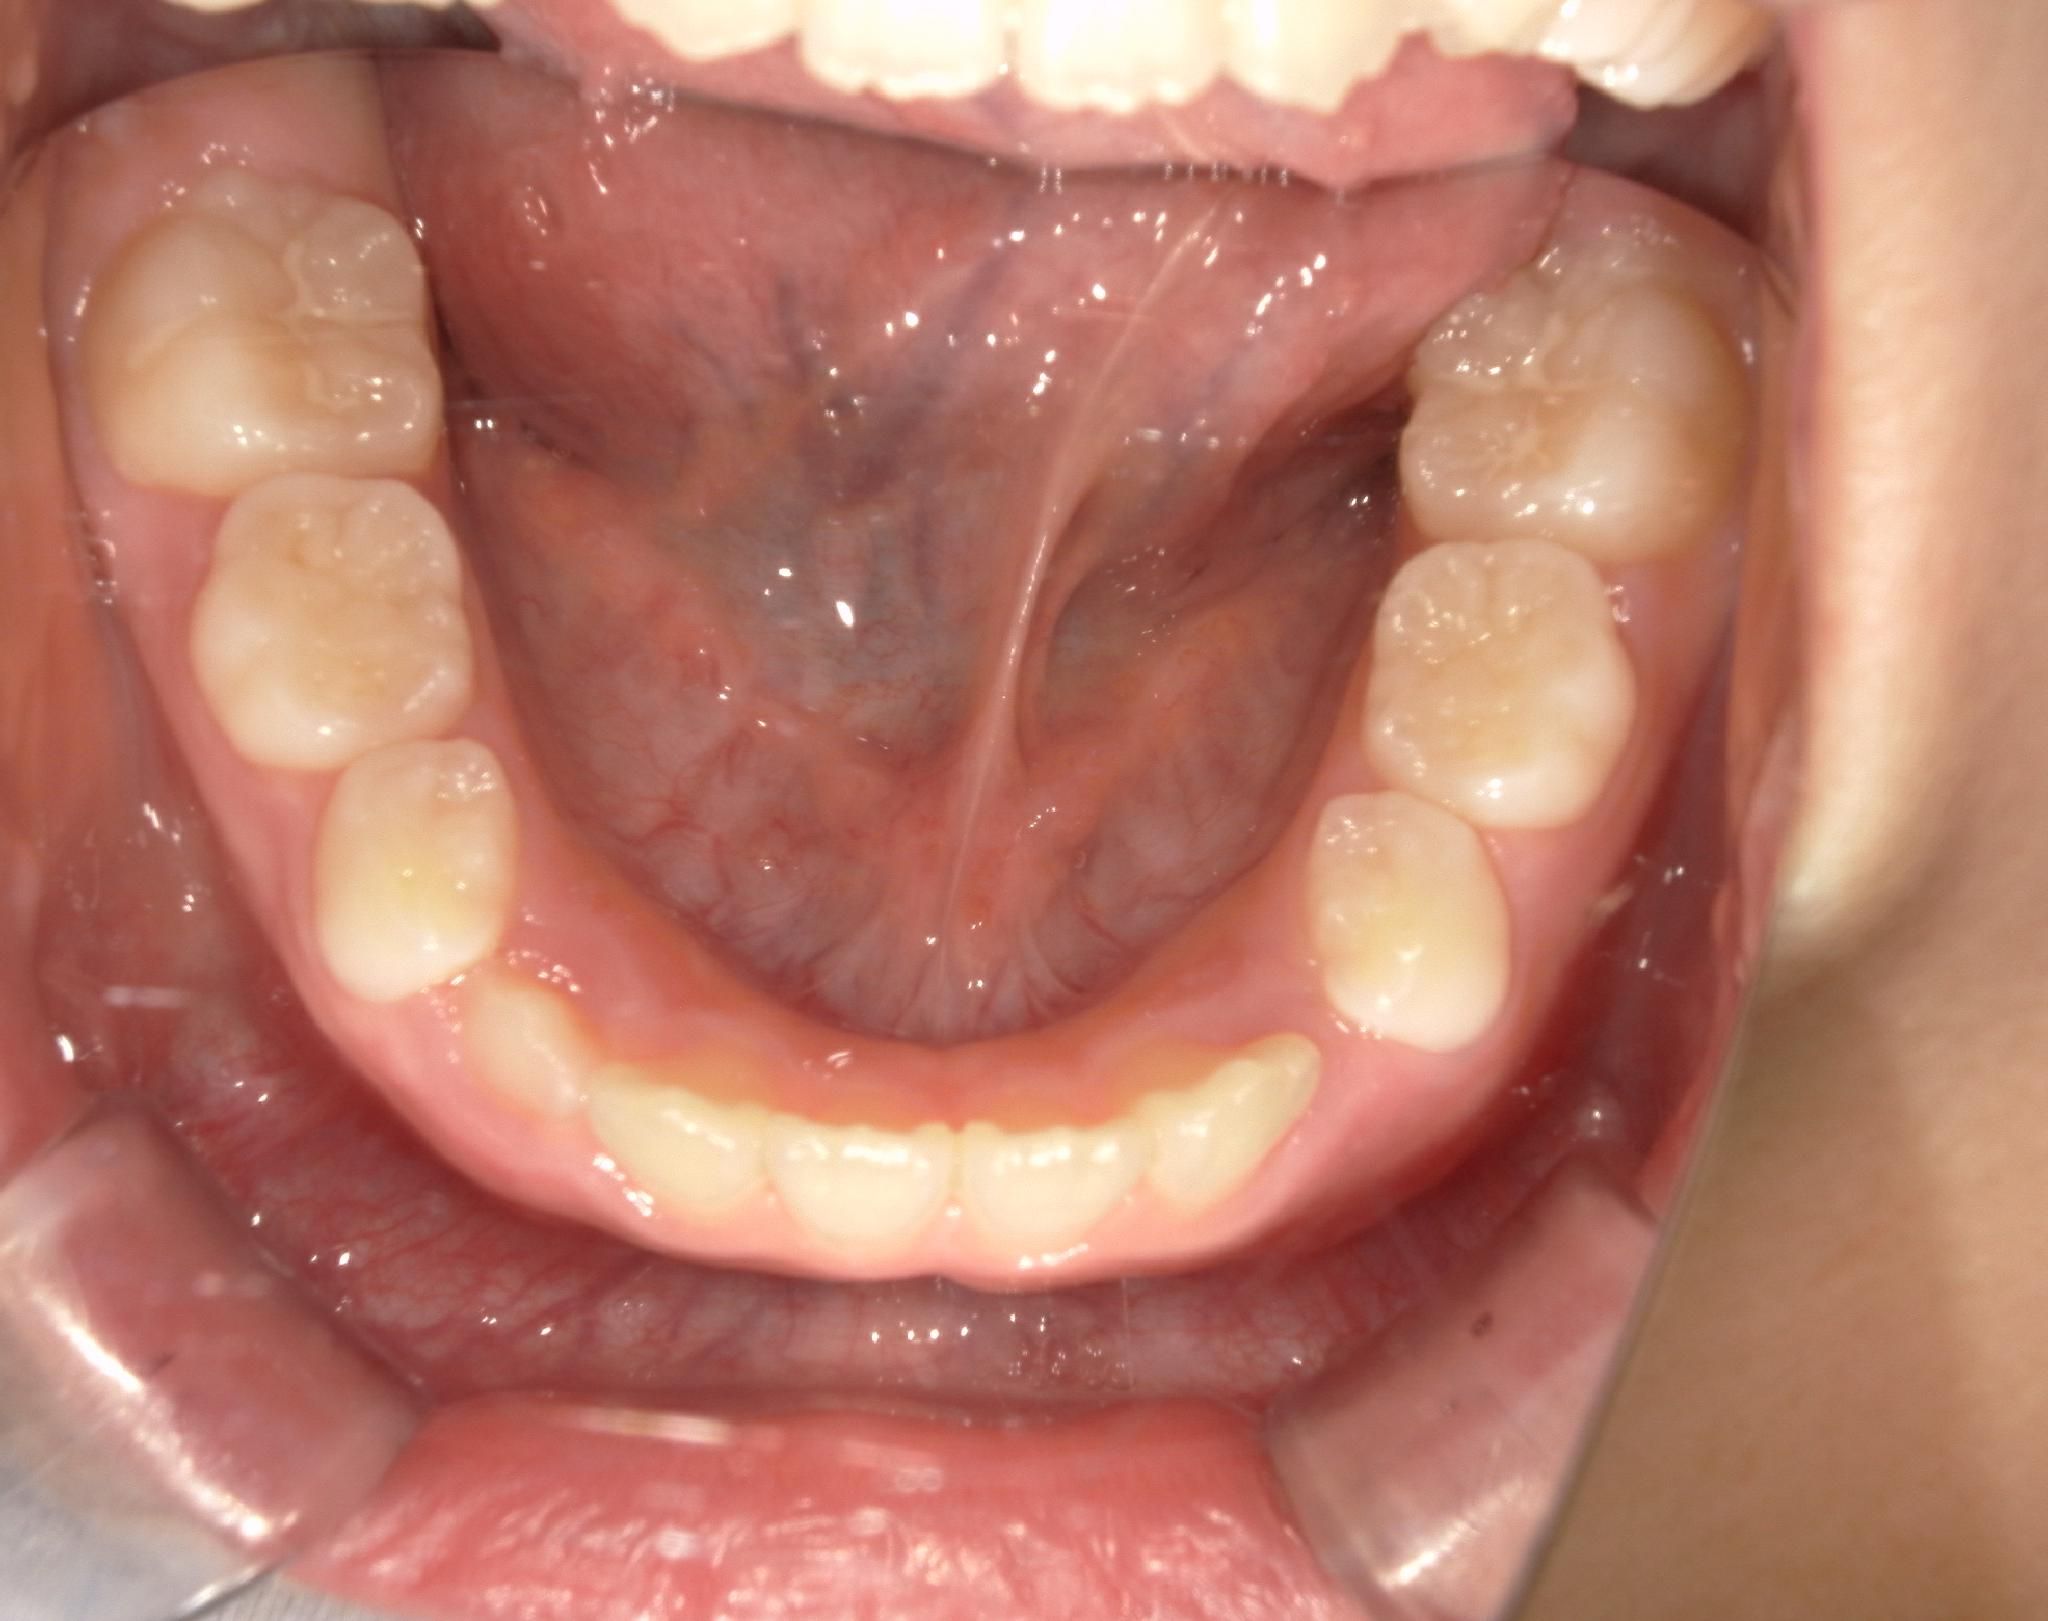

治療前 Before

上の歯並びがガタついています